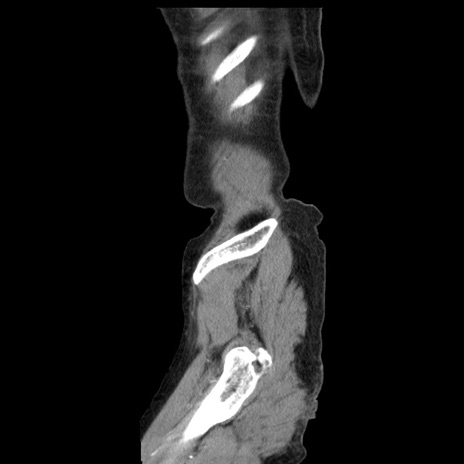

横断像

【症例】80歳代女性

【主訴】腹痛

【現病歴】8時間前から腹痛あり来院。

【既往歴】糖尿病、脂質異常症、子宮体癌にて子宮全摘術

【身体所見】意識清明・会話良好だが腹痛で苦悶様、全腹部にわたって反跳痛と圧痛あり

【データ】WBC 13600、CRP 0.14、LDH 224、CK 90